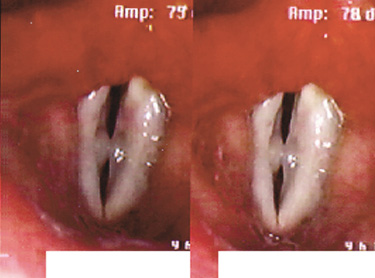

성대낭종이란?

성대낭종은 과도한 음성사용으로 인해 주머니 형태의 양성종양이

점막아래에 형성된 것으로 성대점막의 면을 따라 둥근 공 모양으로 나타나는

표피양낭종과 점액을 분비하는 점액선의 관이 막혀서 생기는

저류낭종으로 분류할 수 있습니다.

표피양낭종은 성대에서의 돌출이 미미하고

저류낭종은 성대점막직하방에서 발생하여

후두 내부로 돌출하는 양상을 띠게 됩니다.